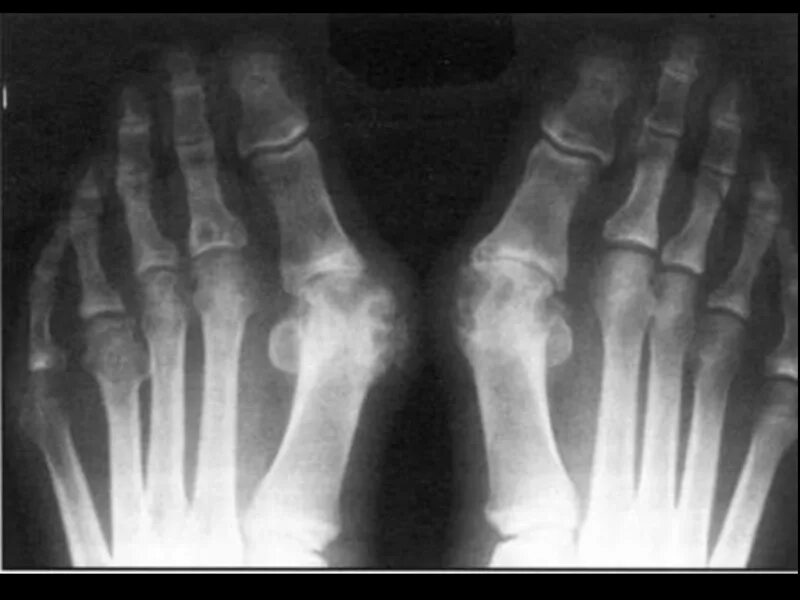

Подагра суставов стопы